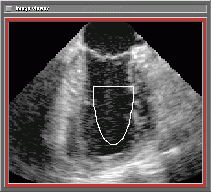

Figure 1. Imaging cone in transesophageal ultrasound

fourdimesional transesophageal ultrasound. This modality uses a transducer

probe that has to be swallowed by the patient to image the heart from the

esophagus. At the tip of the probe a transducer array is positioned that

is capable of acquiring two-dimensional sequences. Rotating the tip of

the probe the imaging plane is rotated so that a cone-shaped volume can

be acquired (Fig.1). For each imaging plane an image sequence of one heart

beat is acquired. Resorting the images one obtains for each moment of the

heartbeat one volumetric dataset.